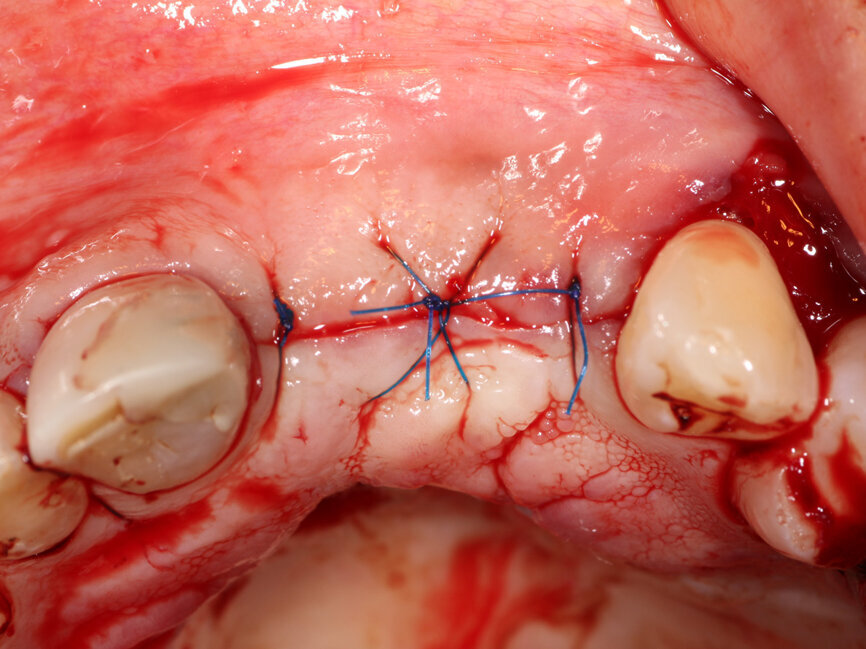

A 2-mm-thick piece of Flexo-Plate Plus (Osteolife Biomedical) sized 15 by 30 mm was checked over the site to ensure adequate coverage of the defect and extension beyond its lateral borders (Fig. 9). The Flexo-Plate Plus is a bendable, partially decalcified allograft with a thickness of 0.75 to1.0 mm. The bone matrix composing the Flexo-Plate is ultimately resorbed by the body, eliminating the need for surgical removal of the matrix. This would serve to stabilize the graft to be placed into the facial defect and upon healing become the new facial cortical plate. The plate comes predrilled with holes through the plate on the left and right aspects to accommodate fixation screws. The Flexo-Plate Plus was soaked in saline to make it pliable and more easily adapted to the ridges curvature. This was adapted to the arch and fixated with a single titanium screw on the left distal to the canine and on the right distal to the right central incisor (MedEquip Dental Supplies, Jupiter, Fla.) (Fig. 10). The graft mixture of PRP, autogenous bone shavings and particulate graft had coalesced into a flexible mass in the sterile dish with the consistency of a gummy bear candy and is referred to as “gummy bone” (Fig. 11). This was carried intraorally and packed between the fenestrated facial plate and the stabilized Flexo-Plate to create what would be the new ridge width dimensions when healing had completed (Fig. 12). The graft and Flexo-Plate were covered with a PRP membrane (also referred to by some authors as PRF), which would act as a short-term barrier to prevent soft tissue ingrowth and a source of growth factors while the graft was healing and maturing (Fig. 13). The flap is reapproximated in a tension-free manner, and the margins are fixated with 5-0 Polypropylene sutures in an interrupted pattern (Fig. 14). Post-op instructions were given, and a booklet with instructions was provided to the patient.[1] These instructions included directions to apply the ice bag over the affected area 20 minutes on and 20 minutes off for two to four hours, to help prevent the development of excessive swelling and discomfort; avoid hot liquids and foods during the first 24 hours following surgery and then warm salt water rinses four to five times daily for the next week. The patient was prescribed 24 tabs of Vicodin (5mg hydrocodone bitartrate /30mg acetaminophen) and instructed to take one tablet every six hours for pain. A prescription for a Medrol Dose Pack was also given, and the patient was instructed to take as the pack recommended.

Fig. 14: Flap is closed without tension using 5-0 Polypropylene suture (Riverpro, Osteolife Biomedical, Jupiter, Fla.) in a simple interrupted pattern.